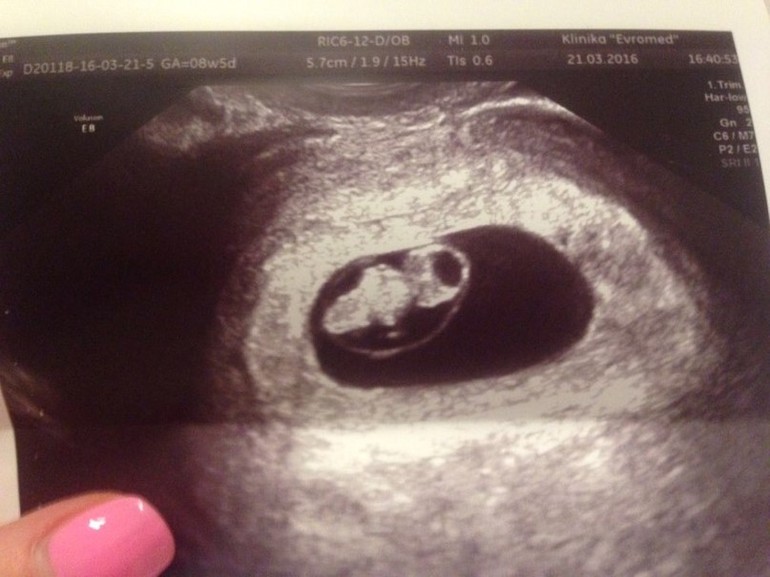

Анна 10 лет Девчушечки мои!!! Нас услышали!!! Спасибо каждой из вас за каждое доброе слово!!! За ваши комментари Посмотрите еще 20 записей на эту тему Отменить Ответить Katrinka Поздравляю! Такой пупсик на узи, ми-ми-ми!! Легкой вам беременности и родов! 22.03.2016 Ответить Анна Спасибо вам большое!!! 22.03.2016 Ответить Naddy Вот она малышечка растет ))))) Давайте набирайте обороты! а тут рррраз и рожать не за горами )))) 22.03.2016 Ответить Анна Спасибо большое!!! 22.03.2016 Ответить Good lady Ну вот:))) смотри у тебя теперь и срок совпадает с кружком на бб здоровья побольше!!!! 22.03.2016 Ответить Анна Спасибо огромное!!! 22.03.2016 Ответить Нас увидели!!! Всем спасибо за советы и поддержку!!! Мы счастливы)))) Спортивная весна)) Удобство и комфорт))) Чаты Беременных Выберите чат: Январята-2026 Февралята-2026 Мартята-2026 Апрелята-2026 Майчата-2026 Июнята-2026 Июлята-2026 Августята-2026